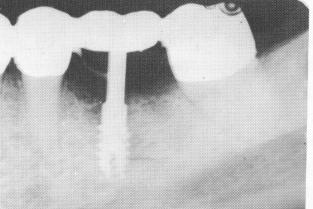

The restoration was tried in the mouth before the implant was inserted, and all necessary adjustments were accomplished (Fig. 8-79). The restoration was then removed, and the vent-plant with a Dacron sleeve was screwed into the bone (Fig. 8-80). (It was hoped that the porous character and slightly irritating quality of the Dacron would pro-mote closer adaptation of the collagenous tissue around the post. Approximately three dozen cases using Dacron sleeves screwed into bone have been done, and all are still in the mouths functioning well. The results are still unsubstantiated by tissue biopsies.) The restoration was then cemented into position with hard cement (Fig. 8-81) and radiographed (Fig. 8-82).

Fig. 8-82. A postoperative radiograph showing the pre-fabricated restoration locked into the existing bridge sup-porting the implant.